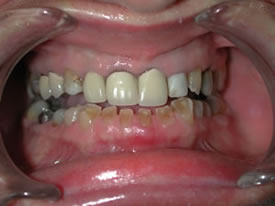

| Notice how the reconstruction affects

not only the occlusion (the way her teeth fit together), but

also the way her smile is expressed throughout her lower face! |

Before